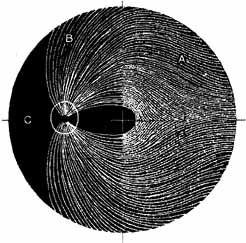

Pupillary dilation and reduction of accommodation occur when parasympathetic innervation to the globe is damaged. When the damage occurs at or distal to the ciliary ganglion, Adie's pupil results. The pupil contracts poorly to light but better to accommodation. The pupil movements are slow and poorly coordinated (vermiform). Generally there is a reduction in accommodation range. The pupil in such cases develops a supersensitivity to parasympathomimetics such as 0.1% pilocarpine. Orbital trauma, inflammation, and intraocular laser treatment may result in Adie's pupil. Deep orbital dissection lateral to the optic nerve in the region of the ciliary ganglion or around the anterior optic nerve where the short ciliary nerves run may also produce Adie's pupil. The denervation may only be sectoral, resulting in an abnormally contoured pupil which demonstrates slow tonic contracture only in the involved sector. Because the parasympathetics have diverged from cranial nerve III prior to entering the ciliary ganglion, pupillary dilation which contracts with 0.1% pilocarpine is not usually associated with neurogenic ophthalmoplegia (Fig. 19).

Fig. 19 A. A patient underwent endoscopic exploration of the right ethmoid and maxillary sinus for persistent epistaxis. Postoperatively the patient demonstrates right proptosis, restricted extraocular movements of the right eye, and a dilated right pupil. Instillation of 0.1% pilocarpine resulted in miosis on the right and no change on the left. Computed tomography (CT) shows a vessel clip lateral to the optic nerve (arrow), near the position of the ciliary ganglion. B. Coronal CT scan showing the clip lateral to the optic nerve (arrow).